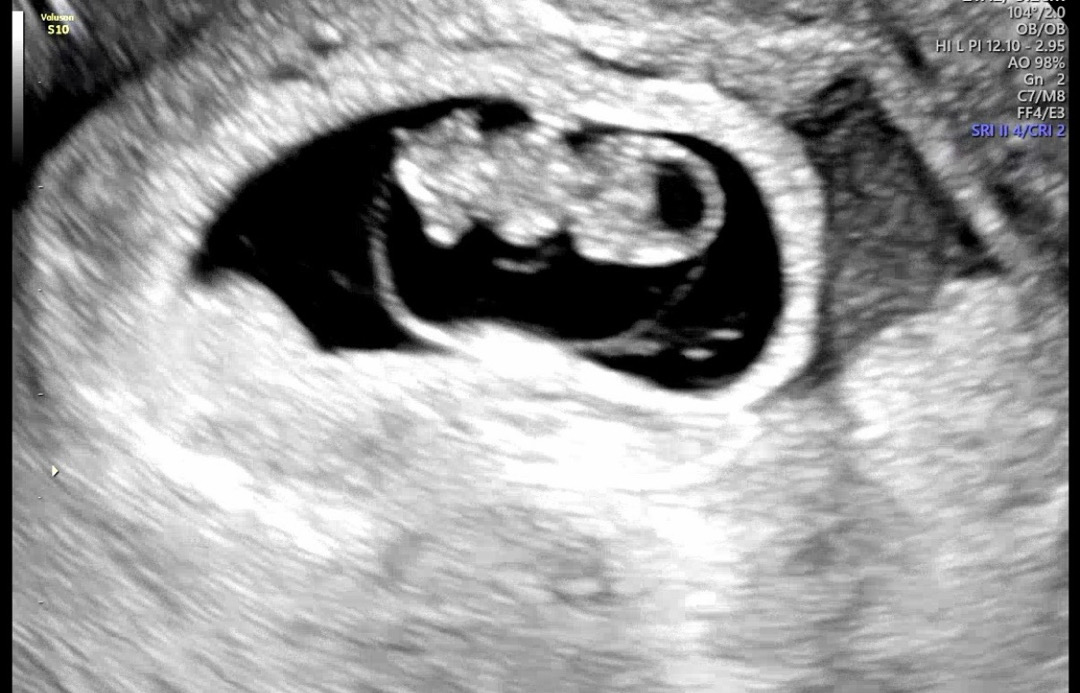

걱정했는데 드디어 심소듣고 하리보봤어요 ㅠ

명절도중 입덧이 사라지고 쎄한 느낌에 오늘은 밑에서 피나는 꿈까지꾸고 걱정 많이 햇거든요 ㅠ 도중에 춈파 보러가려다가 게으른애미라 못가고 오늘 갔는데 원장님이 잘크고있다고 ㅠ흑흑 🫶모두들 건강한 임신되세요🫶